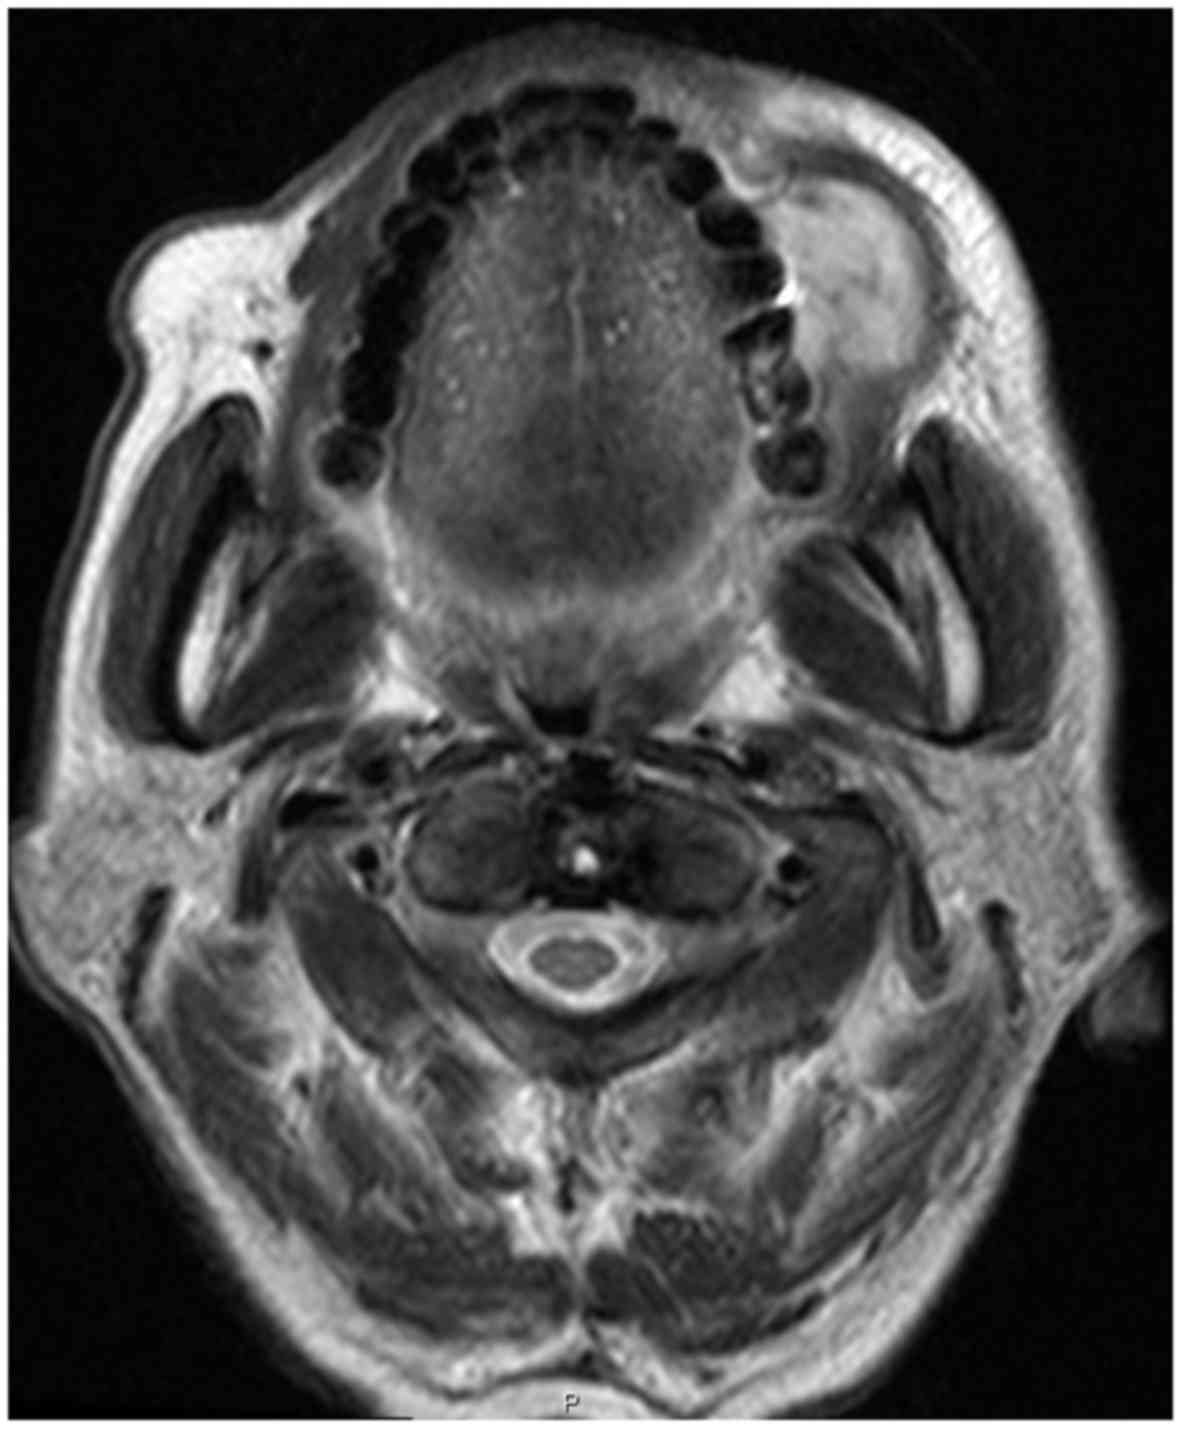

An 85-year-old man presented with a right-sided buccal tumor. One year prior, the patient had been diagnosed with primary lung adenocarcinoma. As the performance status was poor, the patient only received supportive care. The self-reported history of the buccal lesion was rapid growth of the mass over a 2-week period with associated bleeding and pain. The patient was referred to the Oral and Maxillofacial Surgery Unit of the Mito Medical Center (Mito, Japan) for investigation and management. Physical examination revealed a marked swelling on the left upper buccal gingiva (Fig. 1). T2-weighted magnetic resonance imaging also revealed a marked swelling on the left upper buccal gingiva (Fig. 2). A biopsy specimen of the lesion obtained under local anesthesia without complications was sent for histopathological examination. The histopathology of the specimen was morphologically consistent with adenocarcinoma and immunohistochemical staining was positive for cytokeratin-7 and thyroid transcription factor-1, which supported the diagnosis of metastasis to the oral cavity from lung adenocarcinoma. Brain magnetic resonance imaging and chest and abdominal computed tomography scans revealed metastatic lesions in the brain, pancreas, adrenal glands and kidneys. The oral lesion was irradiated, but the response was poor and the patient soon succumbed due to cachexia. Informed consent was obtained from the patient's family for the publication of the case details.

Figure 2.

T2-weighted magnetic resonance imaging showing a mass located in the left upper buccal gingiva.